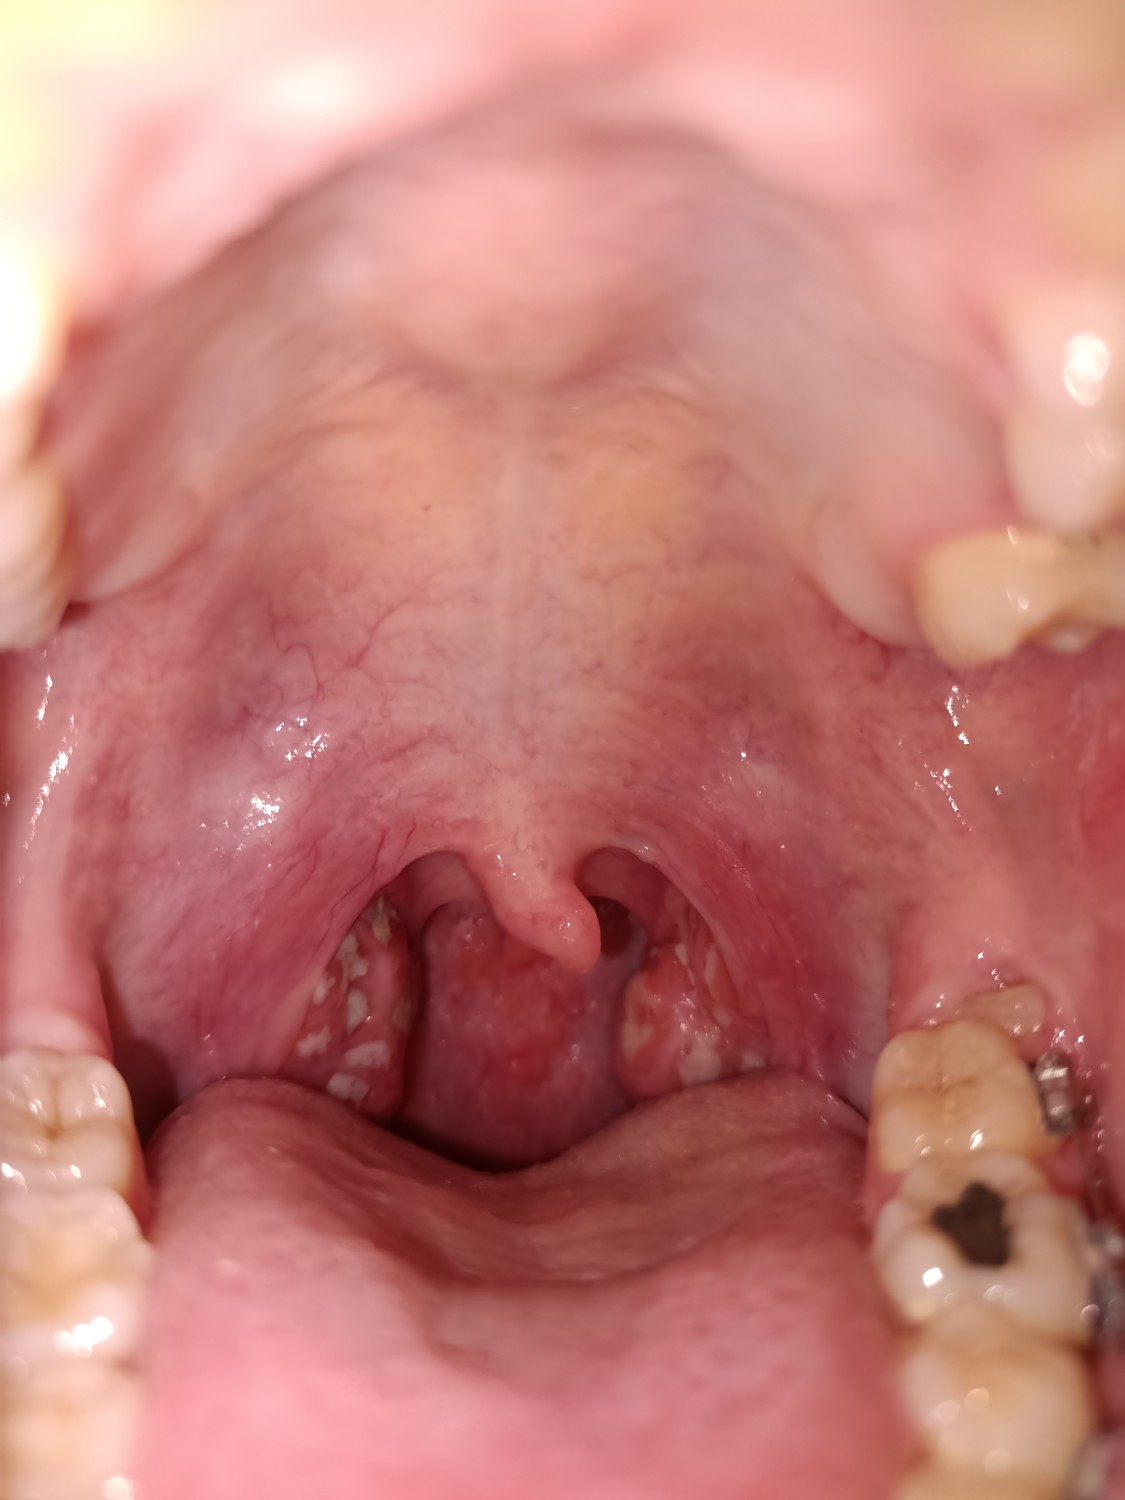

แบบนี้หนองในคอหรือเปล่า เกิดจากอะไร